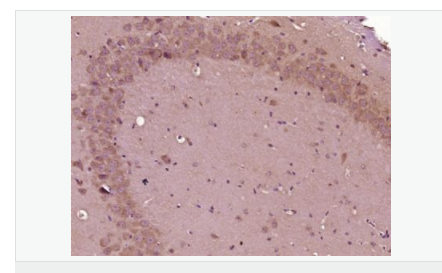

| 產品應用 | WB=1:500-2000 IHC-P=1:100-500 IHC-F=1:100-500 ICC=1:100-500 IF=1:100-500 (石蠟切片需做抗原修復) not yet tested in other applications. optimal dilutions/concentrations should be determined by the end user. |

| 產品介紹 | This gene encodes the epsilon member of the sarcoglycan family. Sarcoglycans are transmembrane proteins that are components of the dystrophin-glycoprotein complex, which link the actin cytoskeleton to the extracellular matrix. Unlike other family members which are predominantly expressed in striated muscle, the epsilon sarcoglycan is more broadly expressed. Mutations in this gene are associated with myoclonus-dystonia syndrome. This gene is imprinted, with preferential expression from the paternal allele. Alternatively spliced transcript variants encoding different isoforms have been found for this gene.[provided by RefSeq, Oct 2010] Function: Component of the sarcoglycan complex, a subcomplex of the dystrophin-glycoprotein complex which forms a link between the F-actin cytoskeleton and the extracellular matrix. Subcellular Location: Cell membrane > sarcolemma. Cytoplasm > cytoskeleton. Tissue Specificity: Ubiquitous. DISEASE: Defects in SGCE are a cause of dystonia type 11 (DYT11) [MIM:159900]; also known as myoclonic dystonia or alcohol-responsive dystonia. DYT11 is a myoclonic dystonia. Dystonia is defined by the presence of sustained involuntary muscle contractions, often leading to abnormal postures. DYT11 is characterized by involuntary lightning jerks and dystonic movements and postures alleviated by alcohol. Inheritance is autosomal dominant. The age of onset, pattern of body involvement, presence of myoclonus and response to alcohol are all variable. Similarity: Belongs to the sarcoglycan alpha/epsilon family. SWISS: O43556 Gene ID: 8910 Database links: Entrez Gene: 8910 Human Entrez Gene: 20392 Mouse Omim: 604149 Human SwissProt: O43556 Human SwissProt: O70258 Mouse Unigene: 371199 Human Unigene: 8739 Mouse Unigene: 185815 Rat Important Note: This product as supplied is intended for research use only, not for use in human, therapeutic or diagnostic applications. |